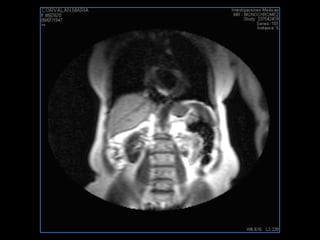

PROTOCOLO abdomen COR T2, AXIAL supresion grasa AX T1 +SAG T2  CON   GADOLINIO :  COR T1+AX T1(DIN) SAT: NO  FASE: RL THK: 6MM  COIL:  GAP: (FACTOR 1.4) 2MM FOV: 40 CM NEX:2 SINCRONIZACION RESPIRATORIA EN 3 O 4 CICLOS ALE

PROTOCOLO pelvis SAG T2, Y FAT SAT (FINOS) AXIAL T1  AX FAT SAT CON   GADOLINIO :  AX T1 Y COR T1 SAT: NO  FASE: RL THK: 3MM  COIL:  GAP: (FACTOR 1.4) 1MM FOV: 40 CM NEX:2 SINCRONIZACION RESPIRATORIA EN 3 O 4 CICLOS ALE

resonancia de abdomen